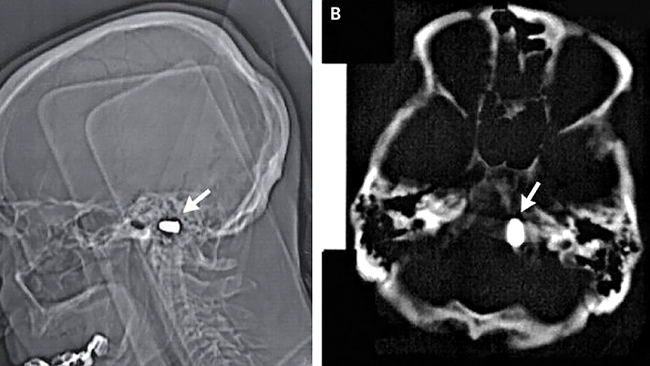

Treptat, rusul si-a revenit, iar de curand a fost supus unor teste RMN din cauza problemelor cardiace. Cu aceasta ocazie, medicii i-au descoperit glontul la baza cutiei craniene, dar spre surprinderea lor creierul barbatului nu a fost afectat.

In cazul barbatului de 85 de ani, glontul a ramas blocat intr-o zona „sigura” a cutiei craniene si ar fi fost putin probabil sa cauzeze complicatii.